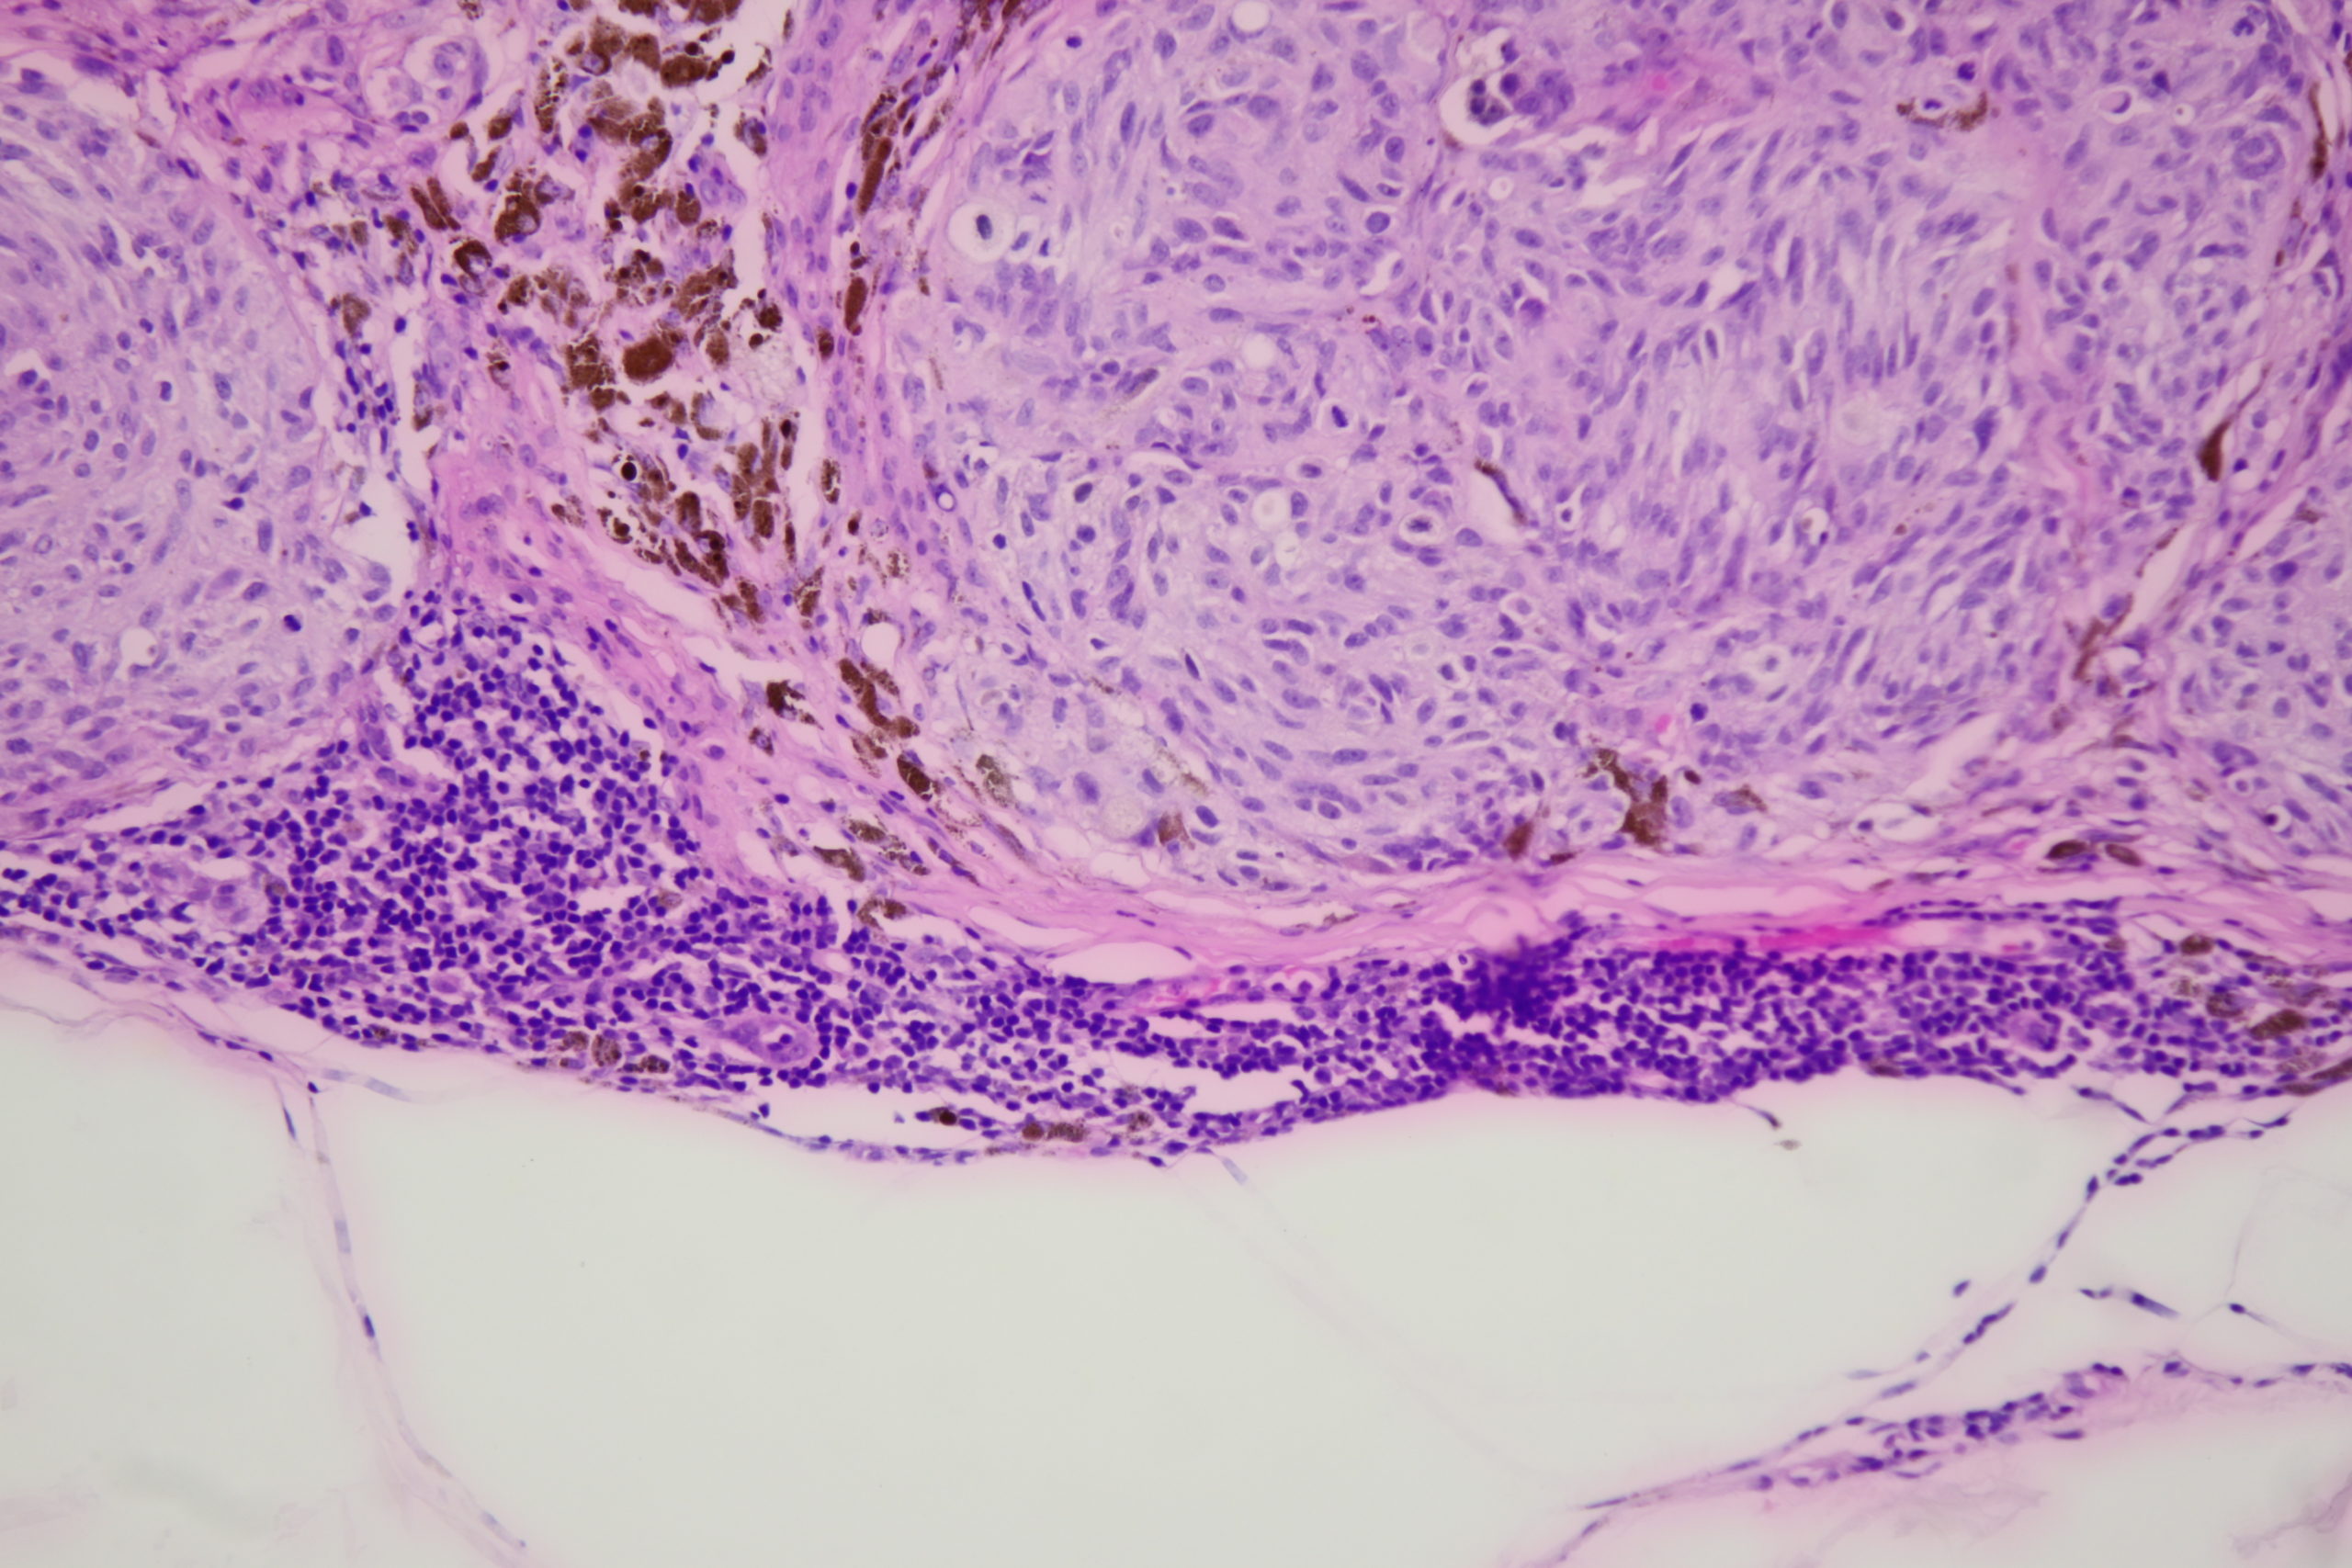

Site: Back

Diagnosis: Melanoma nodular

Pigmented lesion upper back

This lesion was noted during a routine skin examination in an elderly patient on immunosuppressives for an autoimmune disease.

The lesion was a 0.55 mm thick Clark level 3 nodular melanoma.